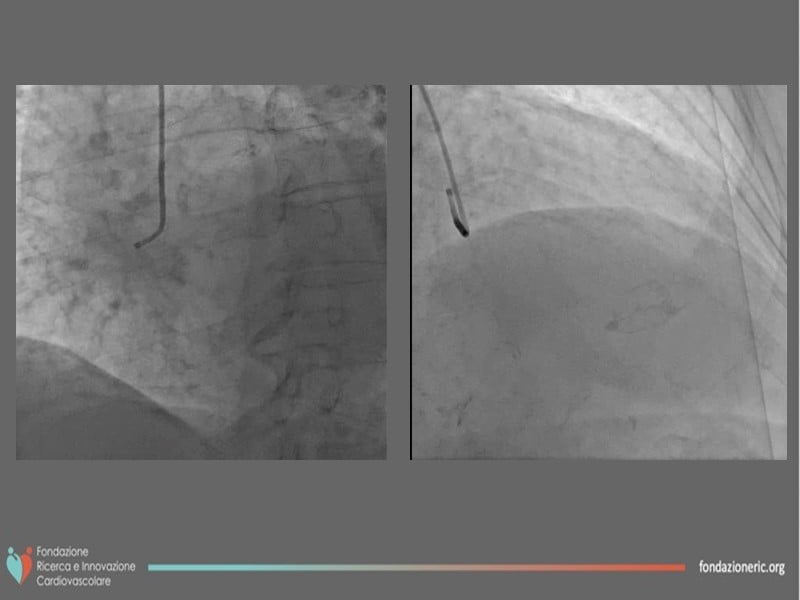

Thanks to the different interventions of this EuroPCR 2022 session, understand the role of paclitaxel DCB in modern era interventional cardiology, the differences, and advantages versus DES, the role of blended therapies in CLS, and learn how to correctly prepare the lesion and obtain the best from this technology on the long term.